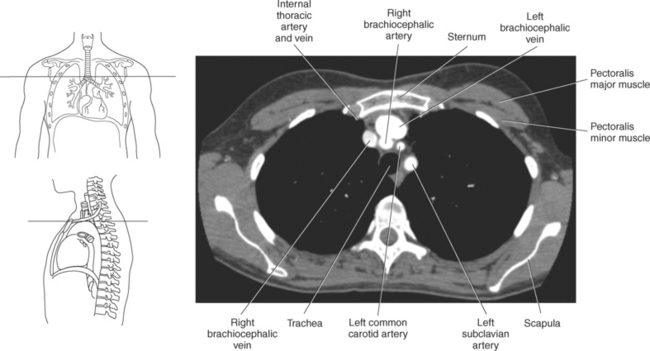

The three main branches of the aortic arch are the brachiocephalic trunk, left common carotid artery, and left subclavian artery (Figure 6.84). The brachiocephalic (innominate) trunk is the first major vessel and the largest branch arising from the aortic arch. It ascends obliquely to the upper border of the right sternoclavicular joint, where it divides into the right common carotid and right subclavian arteries (Figures 6.85 and 6.86). The right common carotid artery ascends the neck lateral to the trachea to the level of C4, where it divides into the right external and internal carotid arteries. The right subclavian artery curves posterior to the clavicle into the axillary region, where it becomes the right axillary artery. The left common carotid artery is the second vessel to branch from the aortic arch. It arises just behind the left sternoclavicular joint and ascends into the neck along the left side of the trachea to the level of C4, where it bifurcates into the left external and internal carotid arteries. The left subclavian artery arises from the aortic arch posterior to the left common carotid artery and arches laterally toward the axilla in a manner similar to that of the right subclavian artery, where it continues as the left axillary artery (Figures 6.85 through 6.88). The right and left internal thoracic arteries arise from the respective subclavian artery at the base of the neck. They run deep to the ribs, just lateral to the sternum, to supply blood to the anterior portion of the thorax (Figure 6.89). The common carotid arteries supply blood to the head and neck, whereas the subclavian arteries supply blood to the upper extremities.

The superior vena cava receives blood from the head and neck via the internal and external jugular veins and from the upper extremities via the subclavian veins (Figures 6.84 and 6.90). The subclavian veins arise from the axillary veins and course posterior to the clavicles. They receive blood from the external jugular veins before uniting with the internal jugular veins behind the sternoclavicular joints, where they continue as the brachiocephalic veins. The left brachiocephalic vein courses across the midline, anterior to the branches of the aorta, to unite with the right brachiocephalic vein just posterior to the costal cartilage of the right first rib. The union of the two brachiocephalic veins forms the superior vena cava, which empties into the right atrium of the heart (Figures 6.75 and 6.76).

Muscles of the anterior and lateral thoracic region are pectoralis major, subclavius, pectoralis minor, and serratus anterior. Muscles associated with the movement of the upper extremity such as the pectoralis, subclavius, and serratus anterior can also function as accessory muscles for respiration (Figure 6.114 and Table 6.4). For example, the pectoralis muscles (major and minor), located on the anterior surface of the chest, primarily aid in the movement of the upper limb, but the pectoralis major muscle can also act to expand the thoracic cavity on deep inspiration (Figures 6.115 and 6.116). The subclavius, a small triangular-shaped muscle located between the clavicle and first rib acts alone to stabilize the clavicle and depress the shoulder. However, conjointly with the pectoralis muscles, the subclavius muscles act to raise the ribs, drawing them upward and expanding the chest, thus becoming important agents in forced inspiration. Additionally, the serratus anterior muscles aid in respiration. The serratus (sawlike) anterior muscle is visualized on the lateral border of the thorax. It extends from the medial border of the scapula to the lateral surface of the first rib through eighth ribs. The primary action of the serratus anterior muscle is to laterally rotate and protract the scapula. It can, however assist in raising the ribs for inspiration (Figure 6.114; see also Chapter 9).